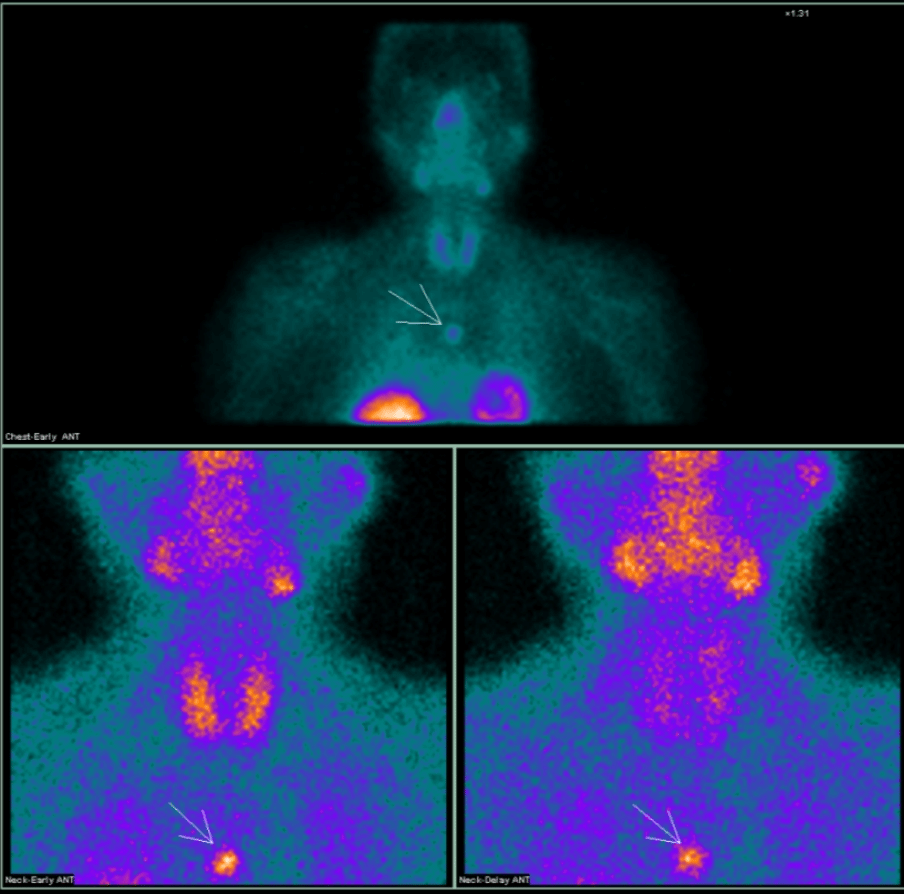

为了明确病变的位置,段阿姨又进行了核医学科的甲状旁腺显像(图5):

左侧甲状旁腺区显像剂浓聚较对侧稍增强,消退缓慢,提示可能为左侧甲状旁腺病变。

进一步的SPECT/CT断层融合显像(图6)显示,左上甲状旁腺形态增大,呈长条形,大小约1.3cm×0.6cm×4.5cm,并伴显像剂异常浓聚,考虑为功能亢进的甲状旁腺病变,首先考虑腺瘤。